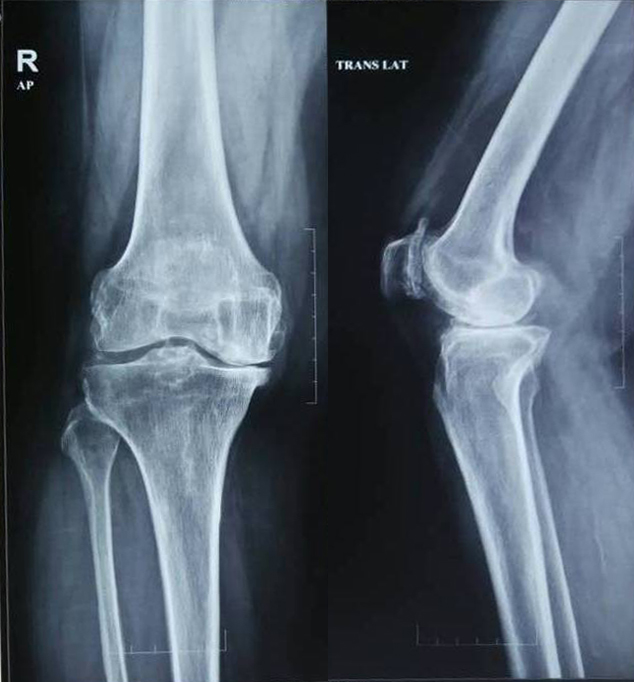

Diacerein-Before treatment

Diacerein-After treatment

X-Ray 2: The anteroposterior and lateral view of the knee joint before and after diacerein treatment

X-ray 2 shows knee joint of osteoarthritis patients before and after treatment with diacerein. Pre-treatment X-ray shows medial intercondylar joint space and femeropatellar joint space narrowing with subchondral sclerosis and osteophyte formation suggestive of severe Osteoarthritic changes. Post-treatment with diacerein shows no significant improvement radiologically.

S-adenosyl methionine-Before treatment

S-adenosyl methionine-After treatment

X-Ray 3: The anteroposteiror and lateral view of the knee joint before and after treatment with S-adenosyl methionine

X-ray 3 shows the knee joint surface before and after treatment of S-adenosyl methionine. Pre-treatment X-ray shows mild narrowing of medial intercondylar joint space with subchondral sclerosis and minimal osteophytes. Femoropatellar joint joint space appears narrowed with retropatellar osteophytes. Post-treatment X-ray shows no significant radiological changes observed in the affected knee joint even after 12 w of treatment with S-adenosyl methionine.